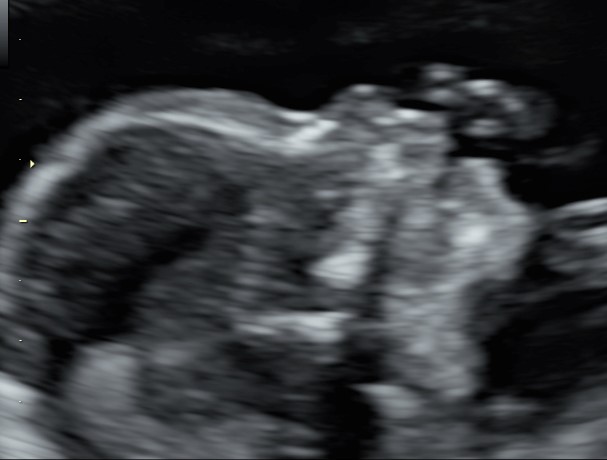

Siamo arrivati al quarto mese. Le incertezze, precauzione e scaramanzie dei mesi precedenti, stanno lasciando il passo a consapevolezza e gioia. L’espressione tipica dei genitori quando guardano il loro “tesoro” a queste settimane è “non pensavo che si vedessero così tante cose e che fosse già così bambino”. Infatti l’impressione ricevuta a queste settimane è di un tesorino alto 14-16 cm e del peso di poco più di 100-180 g, con tutte le sue cosine a loro giusto posto.

Placenta e liquido amniotico sono due parametri essenziali da controllare, strettamente collegate con il benessere fetale.

Un passaggio importante è la valutazione del collo dell’utero, che ha la funzione di sorreggere l’utero che cresce con il suo prezioso contenuto. Con l’ecografia transvaginale è infatti possibile ottenere una misurazione della lunghezza della cervice uterine e vedere se sono presenti modificazioni dell’orifizio interno, che sarebbe la porta di ingresso verso l’utero.